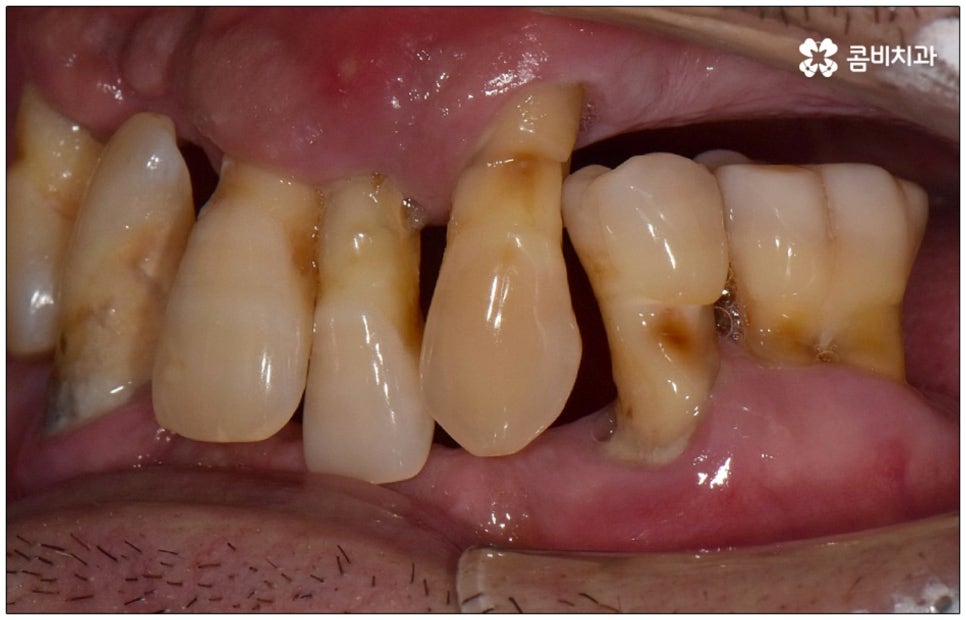

성인 이후 치아 상실의 주된 원인은 바로 풍치인데요, 풍치 즉 치주 질환은 잇몸(치은)을 포함한 치아 주위 조직에 급성 또는 만성으로 염증이 생겨서 손상이 일어난 것을 의미하고 있습니다. 이러한 풍치의 주된 원인은 치태와 치석으로, 음식물 찌꺼기와 치아 표면의 세균막(치태=플라그)이 엉겨붙어 굳어진 치석은 평상시의 칫솔질로는 제거되지 않기 때문에 스케일링 치료를 통해 주기적으로 제거해 줄 필요가 있어요. 치석이 점점 쌓이면 세균이 급증하는 온상이 되어 주변 조직에 염증이 발생하기 쉽고 병증이 심해질수록 치주인대와 치조골까지 손상이 깊어져 결국 치아가 빠지게 되는 거예요. 풍치로 치아를 잃게 되면 임플란트를 심는데도 어려움이 있기 때문에 이렇게 상황이 나빠지기 전에 제 때 적합한 치료를 받을 필요가 있어요. 하지만 잇몸의 경우 병증이 많이 깊어질 때까지 잘 알아차리기 힘든 경우가 많으므로 정기 검진 및 스케일링과 같은 평상시의 관리가 중요하다는 말씀을 드린 거예요.

임플란트 수술을 할 때는 환자의 치아 특징, 상실 원인 및 시기, 턱과 치아의 구조 및 주변 관계 등을 꼼꼼하게 파악한 뒤 식립을 진행하는데, 이와 같이 노인임플란트 수술의 경우에는 특히 현재 건강 상태를 세세하게 체크할 필요가 있으며 이때 환자분께서 고혈압이나 당뇨 등 전신 질환을 앓고 있다면 더욱 주의해야 할 거예요. 또한 평상시 환자분께서 장기 상용하는 약이 있다면 종류에 따라 지혈을 어렵게 하거나 감염의 위험성을 높일 가능성이 있는 약도 있기 때문에 필요하다면 관련 부서와 협진하여 수술 스케줄 앞뒤로 약의 복용에 대해 조정하는 등 이에 대해 정확하게 알아두는 것이 중요하므로 반드시 사전 상담을 통해 의료진에게 고지해 주시길 바라고 있습니다.